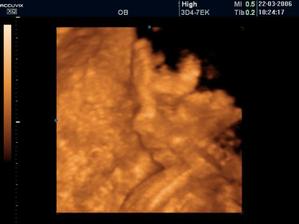

Náš pokladík Viktorko sa narodil 28.7.2006 o 19:20. Vážil 3650 g a meral 52 cm 😉.